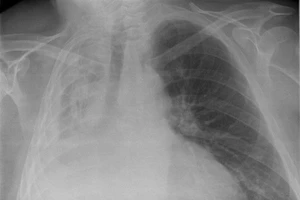

Tràn khí màng phổi sau khi thi hát karaoke